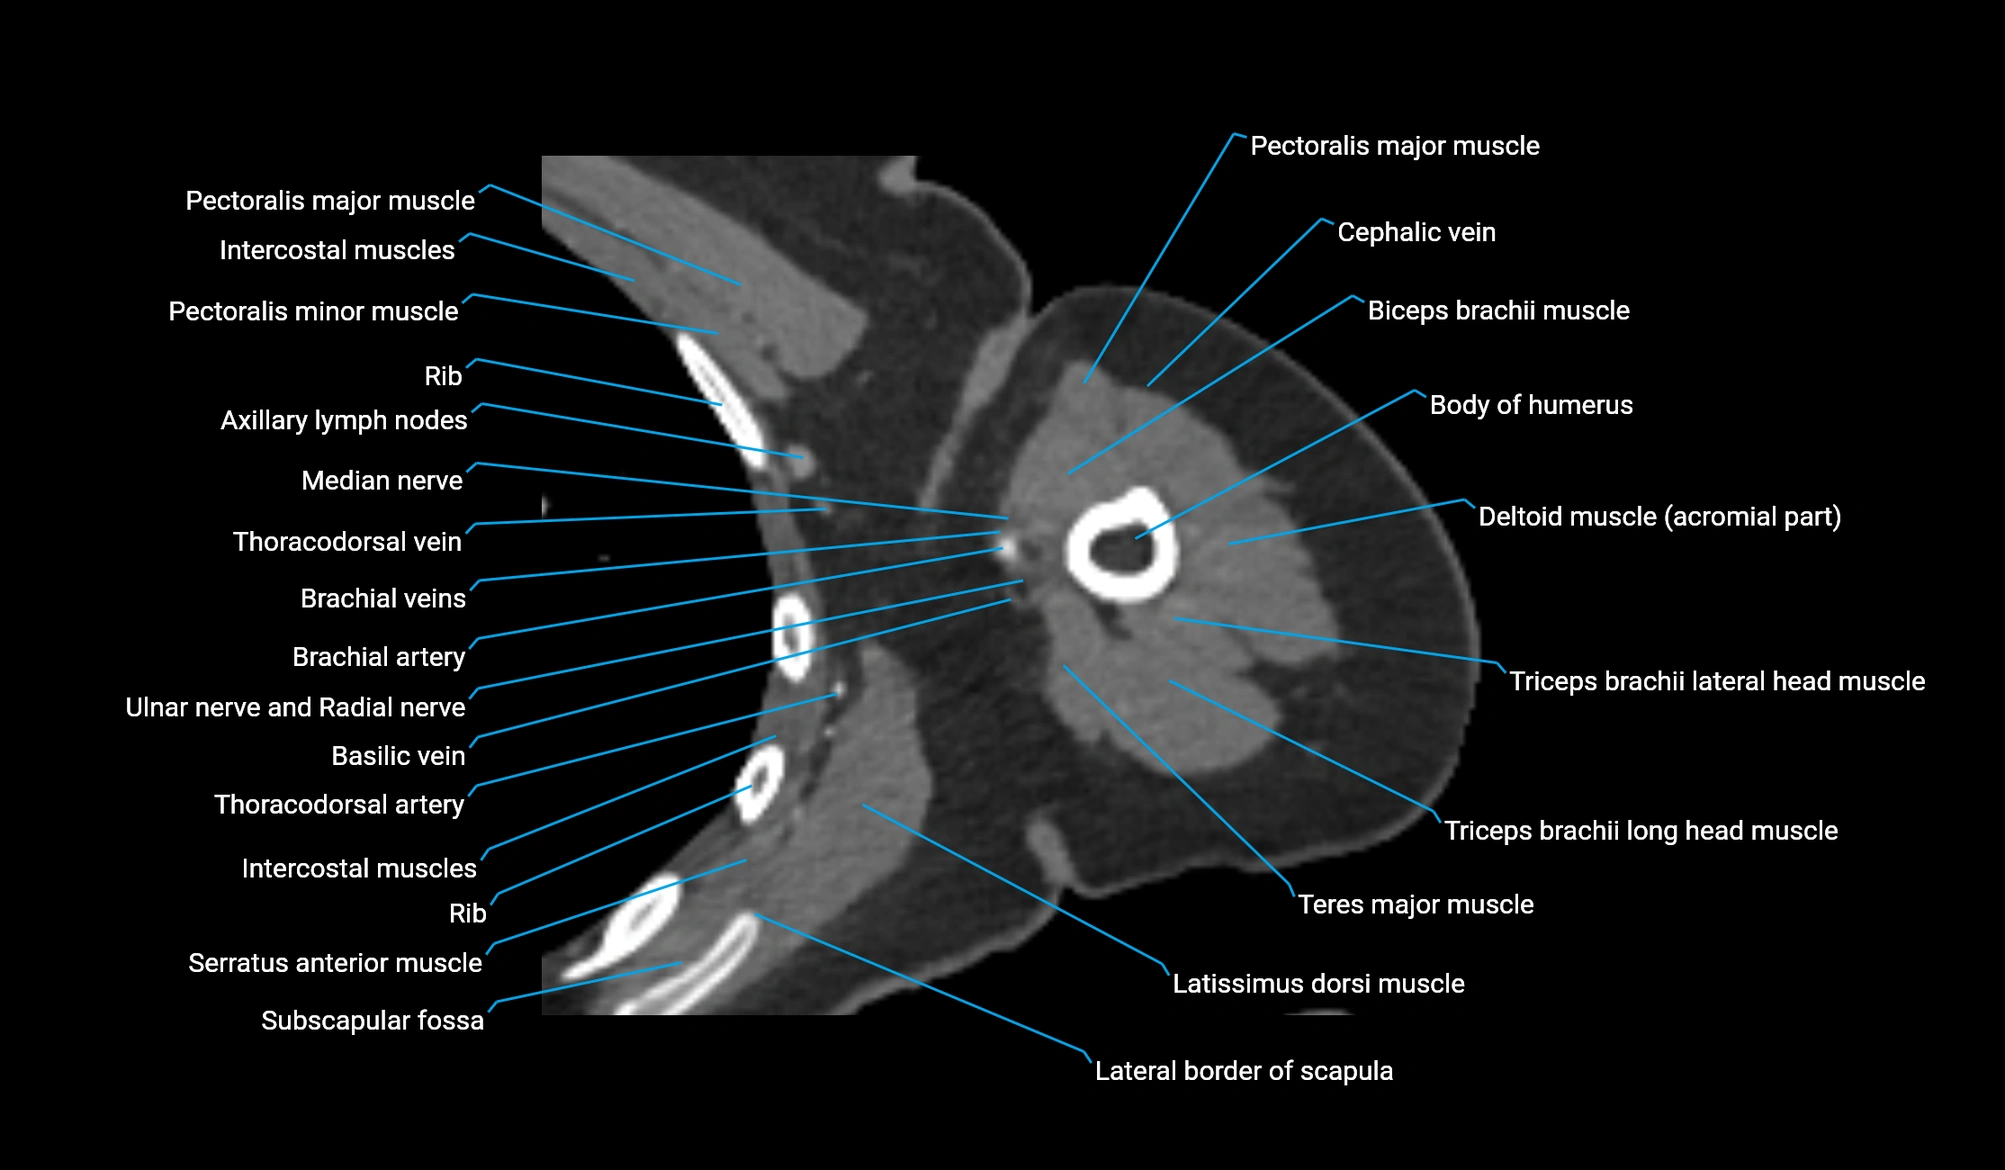

CT image